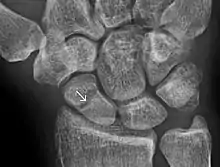

A subtle scaphoid fracture

Scaphoid fractures are often diagnosed using plain radiographs and multiple views are obtained as standard.[9] However, not all fractures are apparent initially.[7] In 1/4 of cases, the clinical examination suggests a fracture, but the X-ray does not show it, even though there is indeed a fracture.[10] Therefore, people with tenderness over the scaphoid (those who exhibit pain to pressure in the anatomic snuff box ) are often splinted in a thumb spica for 7–10 days at which point a second set of X-rays is taken.[7] If a minimally displaced fracture was present initially, healing will now be apparent. Even then a fracture may not be apparent. A CT Scan can then be used to evaluate the scaphoid with greater resolution. The use of MRI, if available, is preferred over CT and can give one an immediate diagnosis.[11] Bone scintigraphy is also an effective method for diagnosis fracture which do not appear on Xray.[12]